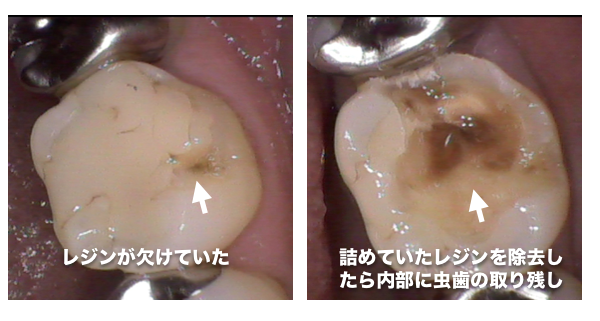

最近治療した歯の内部から虫歯が見つかった症例

以前治療したレジン治療の内部から虫歯の取り残しが見つかった症例

レジン治療の内部で虫歯の取り残しがあった症例

虫歯の治療を受ける場合は、患部の写真を撮って治療してもらえる歯科医院に行くことをオススメしています

当院では治療する場合は、口腔内写真を必ず撮影し、治療前と治療中、治療後で最低3枚以上撮影して、 治療後にどのような状態だったのか写真を撮って説明しています

問題が起きている歯や歯茎を口腔内専用カメラで撮影し治療前と治療後を比較。

治療後にモニターに映して説明しています。

治療途中も虫歯の取り残しがないことを記録で残しているため、治療後に歯に何か気になることがあっても過去の治療内容を見ることができるので安心です。

口腔内写真を取り、患部を拡大することにより、虫歯の取り残しを確実になくししています

A;患部に虫歯の取り残しがないか確認し記録するためです。

治療後は詰め物や銀歯でふさいでしまうためレントゲンで撮影しても小さい虫歯は発見することはできません。

当院は虫歯の取り残しがないようにをしっかり治療し、記録を残しています

歯の内部はどのような治療をしているか患者様はわからないため、治療後は自分の目で虫歯の取り残しがないかどうか確認することをオススメしています

治療していると、過去に治療したレジン治療や銀歯治療の内部で虫歯の取り残しが多く見られます

治療を受ける際は、必ず内部で虫歯の取り残しがないかどうか自分の目で確認できる歯科医院を選択することをオススメしています